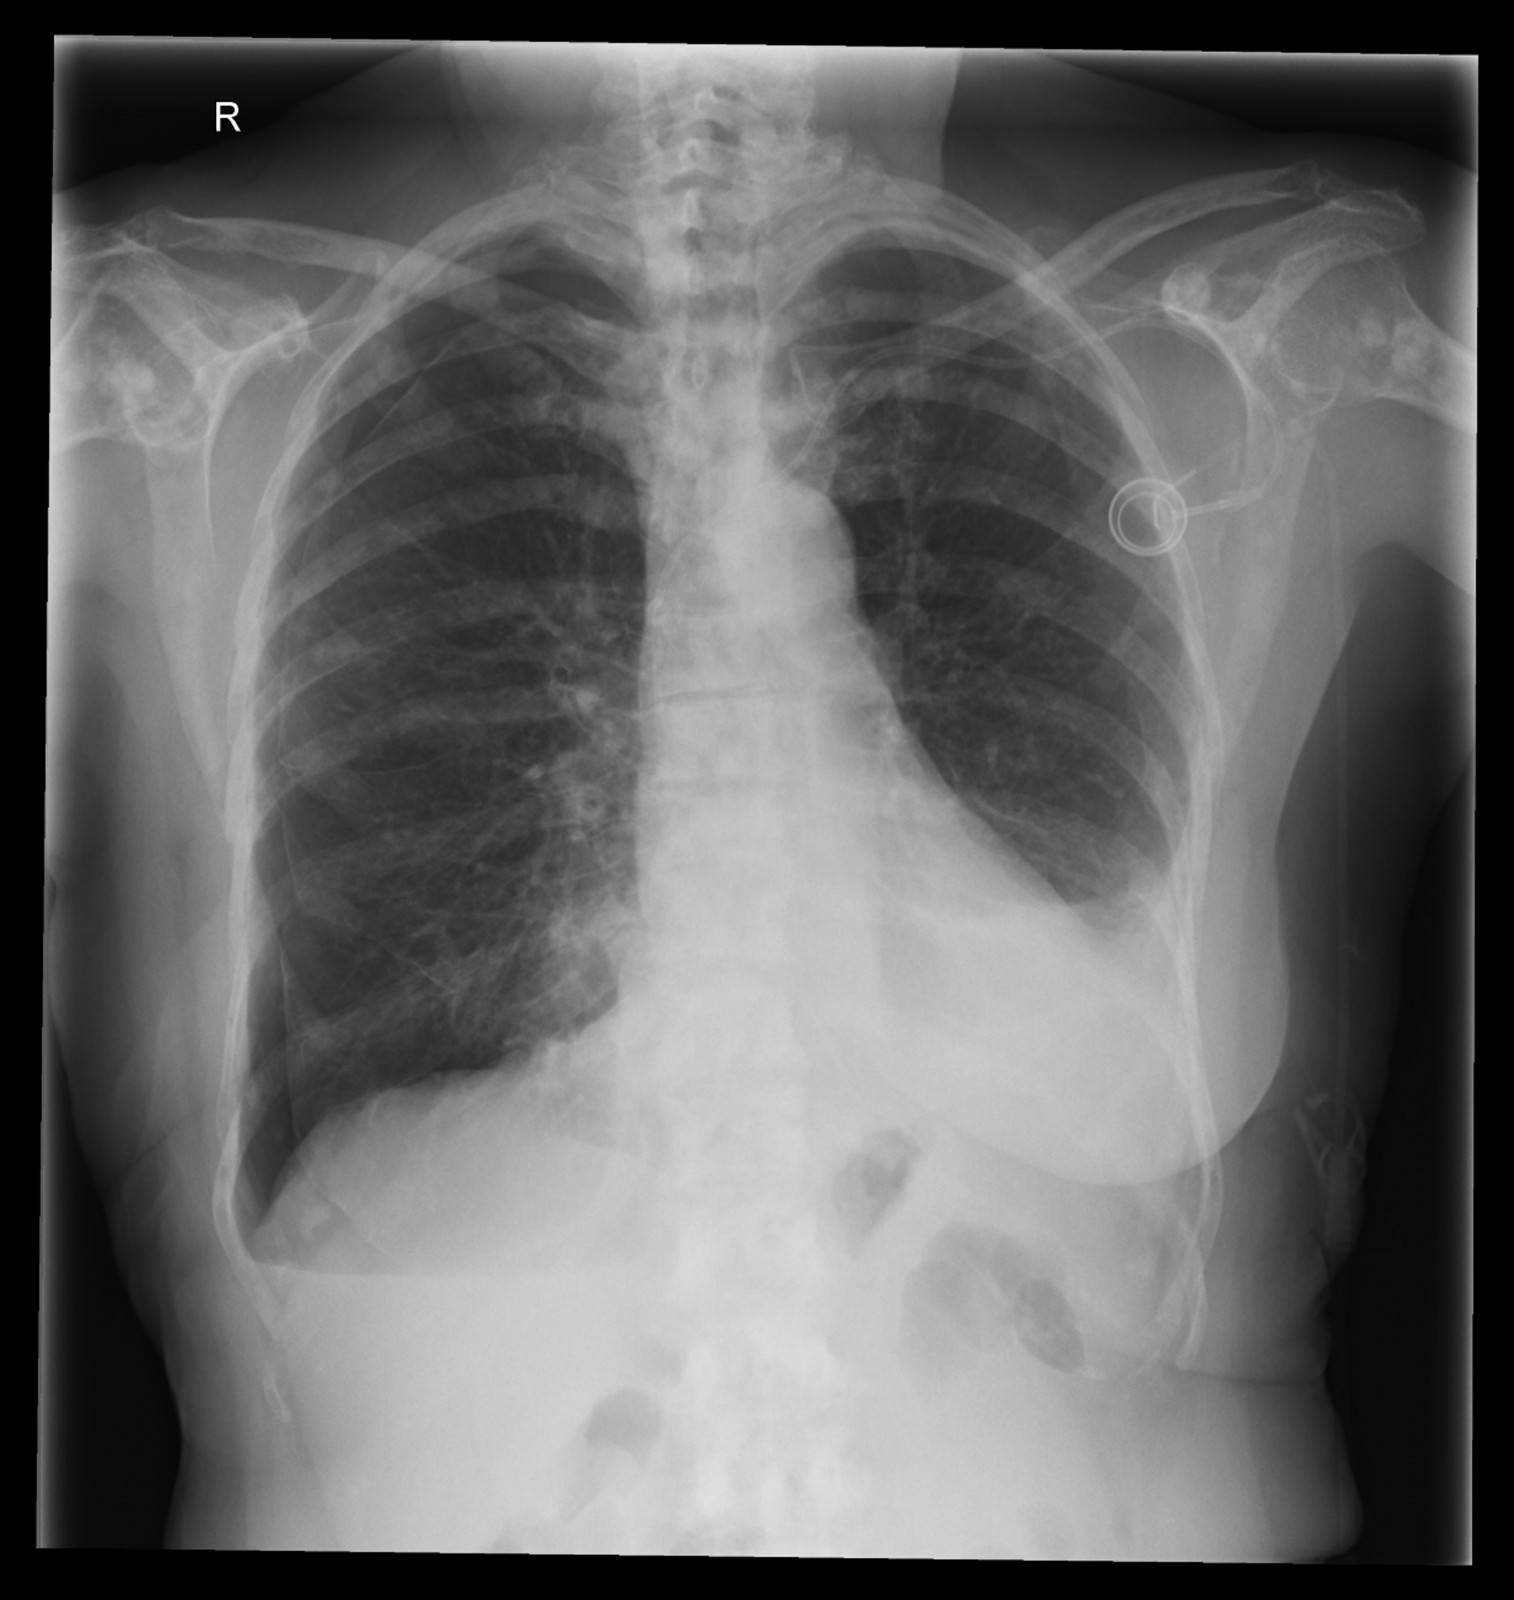

Röntgenfall des Monats Mai 2017 mit Auflösung

74 jährige Patientin mit diffusen Skelettschmerzen und akut aufgetretener Dyspnoe.

Z.n. Mammakarzinom rechts.